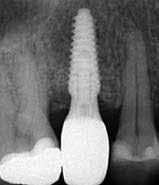

A korai harmicas éveiben járó hölgy rendelőnkbe érkezésének oka a jobb felső nagymetsző fog bizonytalan érzkenysége, elmondása alapján gyermekkorában trauma érte a felső frontrégiót. A frakturált klinikai koronákat kompozittöméssel helyreállították, egyéb kezelést akkor nem tartottak szükségesnek. Az utóbbi hónapokban tapasztalt érzékenység miatt kereste fel rendelőnket. A klinikai vizsgálat (1. és 2. kép) és a CBCT felvétel (3. kép) alapján diagnosztizált külső gyökérreszorpció megoldására a fog eltávolítását, implantátum

bukkális 1. kép: Kiindulási állapot, 2020. január. 3. kép: Kiindulási CBCT felvétel. 2. kép: Kiindulási állapot a palatinális oldal felől.

6. kép: Implantátum-ágy preparáció. 7. a–b. képek: Implantátum behelyezés. 8. kép: A behelyezett implantátum. 10. a–b képek: Azonnali ideiglenes korona készítése. 9. kép: Megfelelő primer stabilitás.

12. kép: A 6 hónapos intraorális kontrollröntgen felvétele.